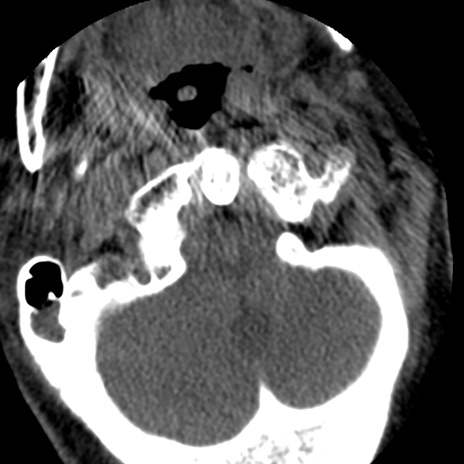

症例50 頚椎CT(横断像)

頚椎CT

冠状断像